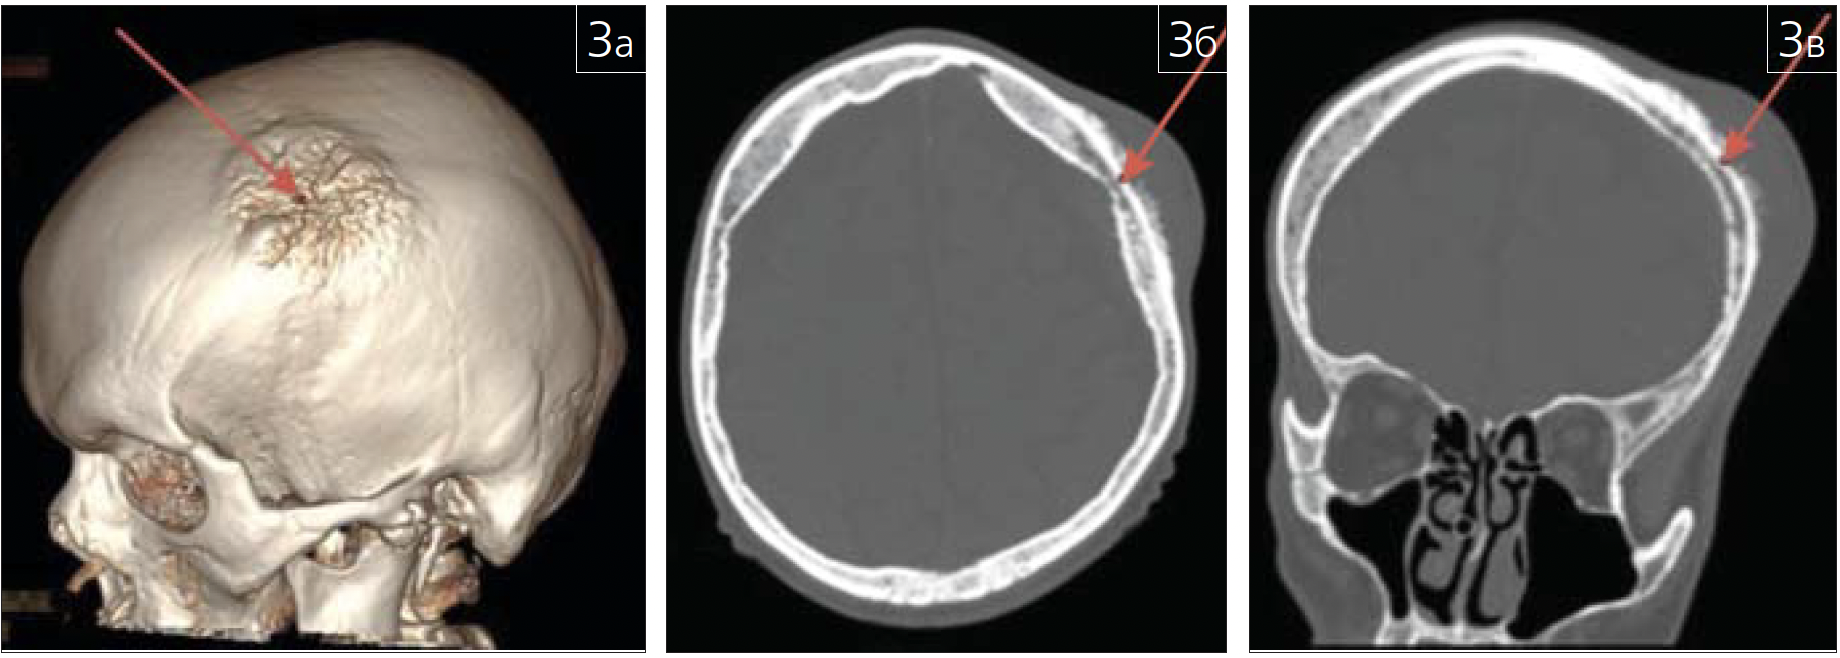

фиброзной дисплазии (рис. 4 а-в; 5),

Рис. 4. Фиброзная дисплазия нижней челюсти слева(показана красными стрелками) на КЛКТ: а – аксиальная проекция;б – атипичная косая проекция